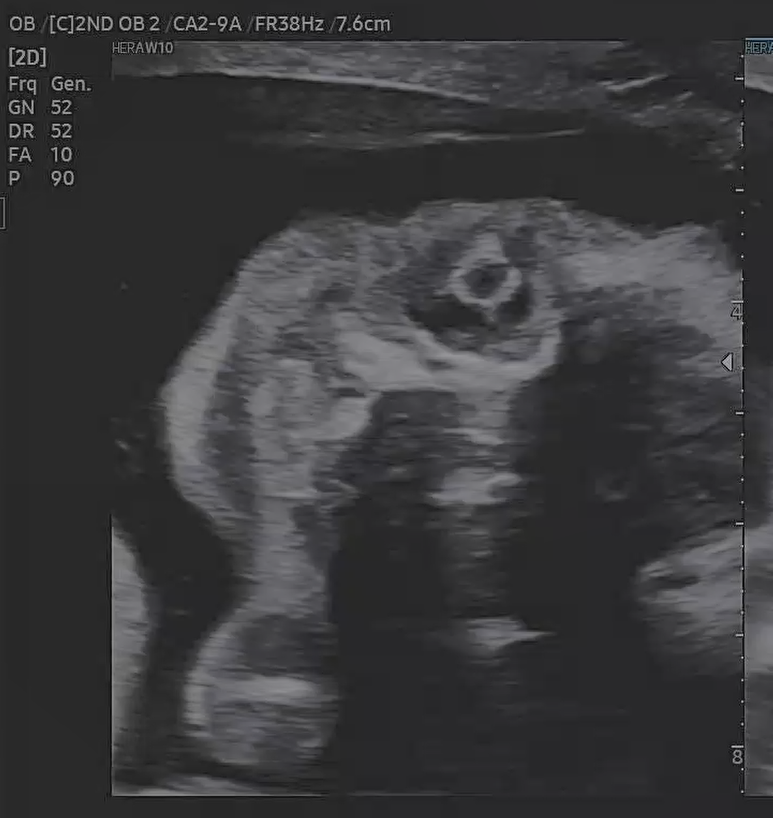

21주 5일, 정밀 초음파 검사가 있는날이었다.

정밀 초음파는 기관들이 잘 형성되어 있는지 초음파로 확인 하는 것이라고 했다.

눈, 코, 입, 심장, 손가락, 발가락 등등 하나하나 확인했다.

흰색 동그라미가 수정체라고 하셨다.

눈을 뜨고있는건가 했는데

감고 있는거라고 하셨다.

심장 판막이 움직이는게

성인과 똑같아서 너무 신기했다.